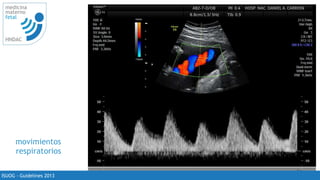

PRF muy bajo

23

ISUOG - Guidelines 2013

PRF adecuado